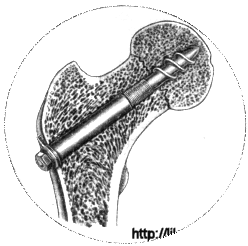

Кортикальный остеосинтез(трехлопастной гвоздь, спицы, винты-фиксаторы Чарнлея, Скальетти, Чаклина, Родина и др.,)

При варусных невколоченных переломах шейки бедра наиболее рационально хирургическое вмешательство.

Существует два основных метода остеосинтеза медиальных переломов шейки бедра: 1) закрытый (внесуставной), когда сустав не вскрывают и место перелома не обнажают; 2) открытый (внутрисуставной) применяемый только в тех случаях, когда закрытая репозиция невозможна (чаще всего при интерпозиции капсулой и при старых переломах). Если рентгенологический контроль за положением отломков и фиксатора во время операции невозможен, также показан открытый остеосинтез. Закрытый остеосинтез проводят под местной анестезией или под наркозом после закрытой репозиции скелетным вытяжением или после одномоментной репозиции на ортопедической столе.

Для остеосинтеза чаще всего используют трехлопастный гвоздь Смит-Петерсена или его модификации. Трелопастный гвоздь обеспечивает стабильный остеосинтез. Линейным разрезом длиной 7-10 см по наружной поверхности бедра обнажают подвертельную область. У основания большого вертела долотом делают зарубки соответственно лопастям гвоздя; под постоянным телерентгенологическим контролем в двух проекциях вводят гвоздь. Он должен пройти по середине шейки бедра в центр головки до кортикального слоя. Исключение составляют субкапитальные переломы, при которых такой метод не обеспечивает надежной фиксации маленького проксимального отломка. Для лучшей фиксации фрагментов кости при субкапитально переломе гвоздь проводят через сустав и вбивают в дно вертлужной впадины так, чтобы конец его выстоял в полость таза на 1 - 1.5 см.